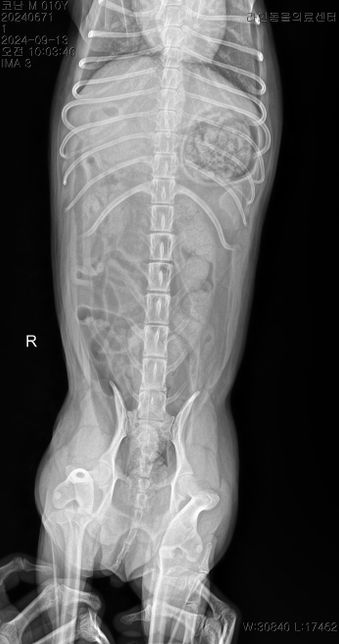

- 반려동물 건강반려동물Q. 강아지 허리 디스크 ct 사진 첨부합니다.. 재질문합니다..한달에 한번 주기로 깨갱 거리면서 특히나 혼자 붕가붕가하고 나서 그러는데요허리 디스크가 어느정도 상태인지 그리고 붕가붕가를 평생 못하게해야하는건지.. 알려주시면 감사하겠습니다....T4-6 vertebrae의 Rt. caudal articular process의 defect 확인됩니다. (→)• T13-L1 vertebrae의 IVDS(intervertebral disc space)가 주변에 비해 좁게 확인됩니다.T13-L1 vertebrae의 IVDS가 주변에 비해 좁게 확인되어 IVDD 가능성고려됩니다.

- 반려동물 건강반려동물Q. 선생님 저희 강아지 허리디스크가 어느정도인가요?한달에 한번 주기로 깨갱 거리면서 특히나 혼자 붕가붕가하고 나서 그러는데요 허리 디스크가 어느정도 상태인지 그리고 붕가붕가를 평생 못하게해야하는건지.. 알려주시면 감사하겠습니다....